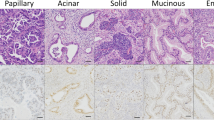

Due to the extremely variegated nature of sinonasal cancers, their classification is quite complex and is continuously being updated [12, 13]. Histologically, SWI/SNF-deficient sinonasal carcinomas belong to the group of sinonasal undifferentiated carcinomas (SNUC); in fact, they have been lumped in the group of SNUC, along with other carcinoma subtypes. SWI/SNF complex-deficient sinonasal carcinomas, defined by the loss of a gene of the SWI/SNF complex, include two main subtypes: SMARCB1- and SMARCA4-deficient sinonasal carcinomas, which have been found to account for four distinctive entities: (1) SMARCB1-deficient sinonasal carcinoma; (2) SMARCB1-deficient sinonasal adenocarcinoma; (3) SMARCA4-deficient sinonasal undifferentiated carcinoma; and (4) SMARCA4-deficient subset (~ 80%) of sinonasal teratocarcinosarcoma [14].

SMARCB1-deficient tumors are characterized by mutations, deletions and other somatic alterations in the tumor suppressor gene integrase interactor (INI) 1, referred also as INI1/hSNF5, which encodes a subunit of the SWI/SNF chromatin remodeling complex. This deficiency drives a wide range of malignancies, including many mesenchymal and putatively non-mesenchymal tumors [15]. The histologic and immunophenotypic features of SMARCB1-deficient carcinomas are heterogenous in nature. Among others, malignant rhabdoid tumor, renal medullary carcinomas, epithelioid sarcomas, some epithelioid malignant peripheral nerve sheath tumors, myoepithelial carcinomas and myxoid extraskeletal chondrosarcomas. In most cases, the tumor consists of a relatively uniform population of undifferentiated basaloid cells with round nuclei containing dispersed chromatin and variably prominent nucleoli, organized in solid sheets and nests with peripheral palisading [10]. In addition, interspersed rhabdoid/plasmacytoid cells with abundant eosinophilic cytoplasm and eccentrically placed nuclei can often be identified. In approximately one-third of the cases, the tumor predominantly consists of these rhabdoid/plasmacytoid cells. There is no evidence of squamous differentiation and no signs of dysplasia of the surface epithelium [16]. Cytological smears show groups of cohesive monomorphic polygonal cells with varying amounts of cytoplasm in rhabdoid/plasmacytoid cells, uniform nuclei with tiny nucleoli and delicate chromatin, but neither hyperkeratinization, nor other signs of squamous differentiation can be observed. Mitotic figures and apoptotic bodies are frequently detected, along with frequent background necrosis [17, 18].

SMARCB1-deficient carcinomas are inherently positive for cytokeratins (CKs), including CK5 and CK7, while p63 is expressed in approximately half of the cases [10]. Neoplastic cells lack nuclear expression of SMARCB1 (i.e., INI1), while the immunostaining is retained in fibroblasts, endothelial cells and inflammatory cells. Focal positivity for neuroendocrine markers, including the cluster of differentiation (CD) 56, synaptophysin and chromogranin A, has also been reported [10]. P16 may be occasionally positive; however, high-risk HPV testing has always been negative [10].

A subset of SMARCB1-deficient carcinomas presents glandular differentiation with formation of cribriform structures and tubules containing intracellular and/or intraluminal mucin. Interestingly, foci with yolk sac tumor-like morphology, consisting mainly of microcystic and reticular growth patterns in a myxoid stroma, can also be present [19]. These rare cases have been designated as SMARCB1 (INI1)‑deficient adenocarcinoma [16]. In addition to the loss of INI1 expression, the immunohistochemical profile of these adenocarcinomas includes positivity for CK7, CK20 (focal) and CDX2 (focal), occasionally including yolk sac markers [e.g., glypican-3, alpha fetoprotein (AFP)], as well as germ cell markers [e.g., Spalt-like protein 4 (SALL4)] [20].

Carcinomas with loss of SMARCA4 are extremely rare in the sinonasal tract [21]. These undifferentiated carcinomas consist of nests of monomorphic cells that tend to merge in solid sheets with areas of coagulative necrosis [22]. While in most of the cases neoplastic cells are predominantly large, in some instances the tumor cells resemble those of small cell neuroendocrine carcinoma or tend to be more elongated with neuroepithelial-like elements. These tumors show complete loss of SMARCA4 and retained expression of SMARCB1/INI1, whereas co-loss of SMARCA2 may be present. SMARCA4 carcinomas lack any expression of squamous differentiation markers, but sometimes show expression of neuroendocrine markers [23]. After having excluded other undifferentiated/poorly differentiated malignancies (e.g., sarcomas, melanoma, lymphomas, olfactory neuroblastoma), the differential diagnosis of SWI/SNF carcinomas is mainly against other sinonasal undifferentiated carcinomas and can be performed by using appropriate immunohistochemical markers. NUT carcinoma is positive for epithelial markers (i.e., CKs, p63, p40) and shows a characteristic punctate nuclear immunostaining with the monoclonal NUT antibody [24, 25]. Distinction from SNUC is based on detection of loss of INI1 expression for SMARCB1-deficient carcinoma and adenocarcinoma, or of SMARCA4 (BRG1) for SMARCA4 deficient carcinomas.

Notably, SMARCB1 deficient adenocarcinomas are frequently positive for yolk sac markers including SALL4, alpha fetoprotein, glypican 3 and CDX2. SMARCA4-deficient carcinomas may show positivity for neuroendocrine markers, including synaptophysin, chromogranin and CD56, thus requiring distinction from neuroendocrine carcinomas, which, however, retain SMARCA4 [20]. Finally, a subset of sinonasal teratocarcinosarcomas show loss of SMARCA4, but they can be distinguished from SMARCA4-deficient carcinoma by the presence of sarcomatoid and teratoid tumor elements [26].

The four sinonasal entities described above and imputed uniquely or predominantly to SWI/SNF-deficiency can be identified via histological markers, without the need of gene analysis [14]. In brief, SMARCB1-deficient sinonasal carcinoma lacks gland formation and retains other distinctive traits, whereas SMARCB1-deficient sinonasal adenocarcinoma shows unequivocal glands or yolk sac-like structures; moreover, SMARCA4-deficient sinonasal undifferentiated carcinoma misses glandular or squamous immunophenotypes, whereas SMARCA4-deficient sinonasal teratocarcinosarcoma displays sarcomatoid and teratoid features.